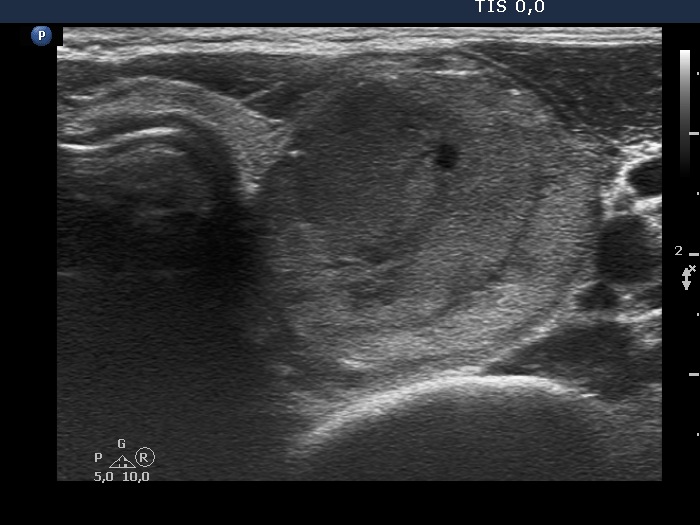

The echogenicity of the nodule - case 2159 (ultrasonographic picture 3)

Lower part of the left lobe, transverse scan.